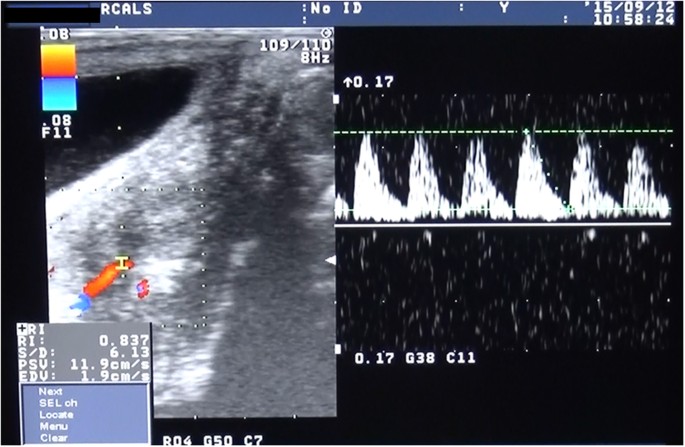

To monitor for potential rejection after the surgery, the size of the transplanted uterus and blood flow in the transplanted uterine artery were determined by transabdominal ultrasonography under anesthesia. Transvaginal biopsy of the transplanted uterine cervix and body was routinely conducted more than once a month or when considered necessary.

In all four recipients, good blood flow through the organ occurred immediately after reperfusion, showing a transition in colour in the uterus from whitish to reddish and pulsations through the uterine artery without uterine congestion (Fig. 4). ICG fluorescent angiography performed immediately after reperfusion also showed sufficient blood flow into the whole transplanted uterus (Fig. 4). In case 1, ICG fluorescent angiography results showed rapidly spreading blood flow toward the left from the right side of the uterus, whereas transabdominal duplex Doppler ultrasonography performed after transplant showed satisfactory blood flow in the right uterine artery but not in the left uterine artery. In other recipients, satisfactory arterial flow in both uterine arteries was observed by transabdominal duplex Doppler ultrasonography after surgery.

All four recipient animals survived for more than 3 months after the surgery without any surgical complications. Although rejection was diagnosed in the biopsy samples within 1 month after the surgery in case 4, within 2 months in case 2 and within 3 months in cases 1 and 3, transabdominal ultrasonography showed pulsatile arterial blood flow in the transplanted uterine artery within 1 month after surgery in all cases (Fig. 5). However, none of the animals resumed periodic menstruation after the surgery.